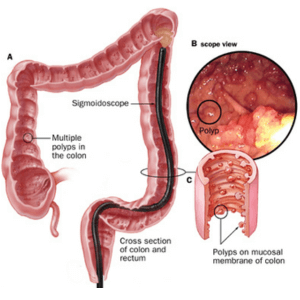

Colon polyps

Familial adenomatous polyposis